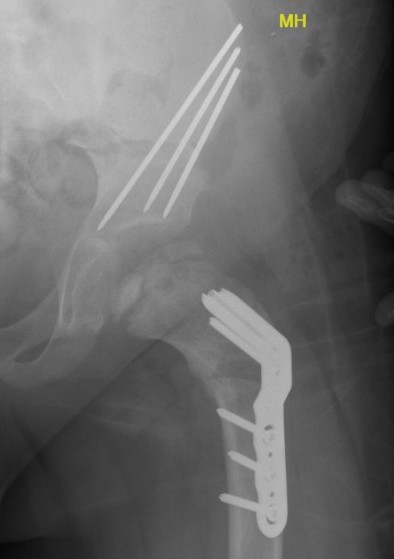

Technique

Patient supine on radiolucent table

- preop antibiotics

- frog leg laterals when needed

Lateral approach

- elevate vas lateralis +/- release proximally with L shaped release

- mark distal and proximal femur with drill holes to check rotation

- place wires up femoral neck short of physis

- use plate to mark osteotomy site

Osteotomy with microsagittal saw 1 cm below lesser tuberosity

- aim for 115o of varus

- avoid excessive varus < 100o to keep greater trochanter distal to femoral neck

- +/- adjust version

- apply plate and fix with screws